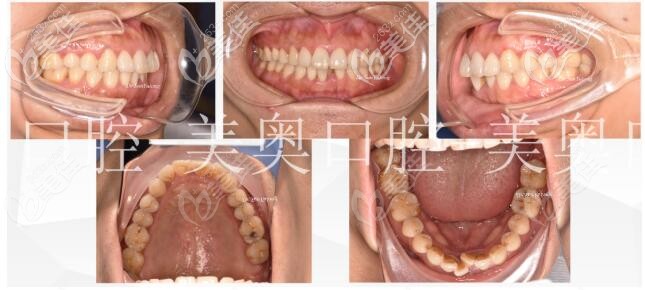

术前照片:

术后照片:

6个月后口内照,之前拥挤、参差不齐的牙齿现在已经有了明显的改善,后续还要在下颌以舌侧保持器进行固定,加强下颌前牙的稳定性。